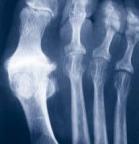

RADIOGRAPHIE

3 stades radiographiques

( cliniquement : hallux dolorosus)

( douleur et enraidissement articulaire)